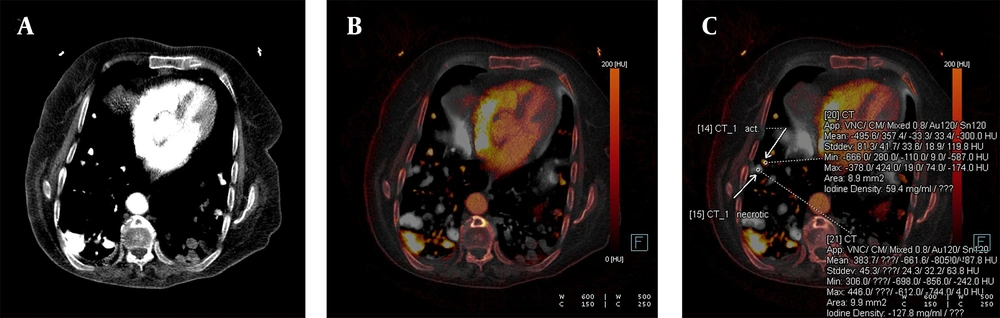

Confirmed metastatic lung nodules originating from colon cancer are shown on the iodine-enhanced image of the patient presenting with shortness of breath. The weighted average image (A), the virtual iodine-enhanced image (B), and the image of the iodine load (C) are shown in dual-energy computed tomography (DECT). On a weighted average image, it is difficult to determine whether the metastatic nodule responds to chemotherapy or not. However, it is easier to identify active and necrotic nodules by inspection on iodinated dual images (white arrows). The detection of the iodine load as 59.4 mg/mL in the active nodule and as negative values in the necrotic nodule are the supporting findings.

Furthermore, another significant aspect of this study is the potential application of DECT as a method for evaluating the treatment response of metastatic lung nodules. In this study, we demonstrated the simultaneous presence of active and necrotic nodules in the lungs of a patient with a primary colorectal tumor and widespread lung metastases. Pulmonary nodules were detected on contrast-enhanced DECT performed for post-chemotherapy treatment response assessment. A significant and apparent iodine load was observed in the active metastatic nodule, whereas the iodine quantity in the necrotic nodule was undetectable. Although this finding was based on a single case, it suggests that DECT may serve as an alternative follow-up imaging method, potentially replacing PET-CT in certain clinical scenarios.